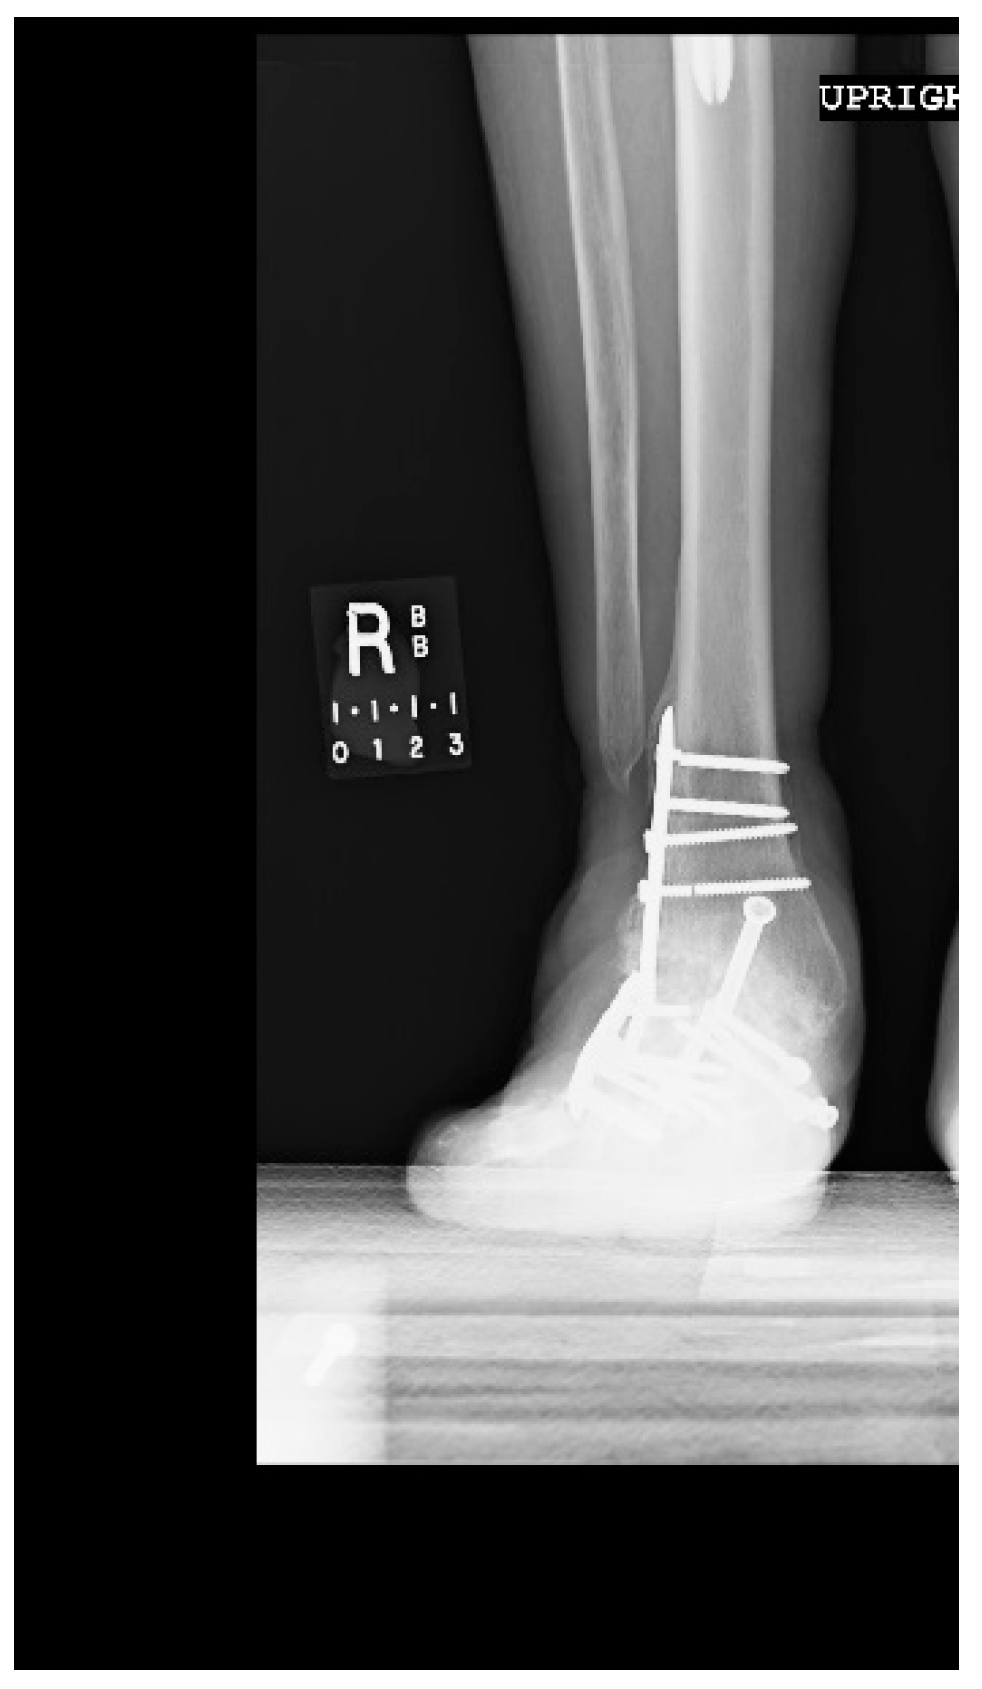

1.1. Case Presentation (Clinical Summary)

1.1.1. Initial Presentation

1.1.2. Operation

1.1.3. Post-Operative Follow-Up

1.1.4. Post-Operative Imaging